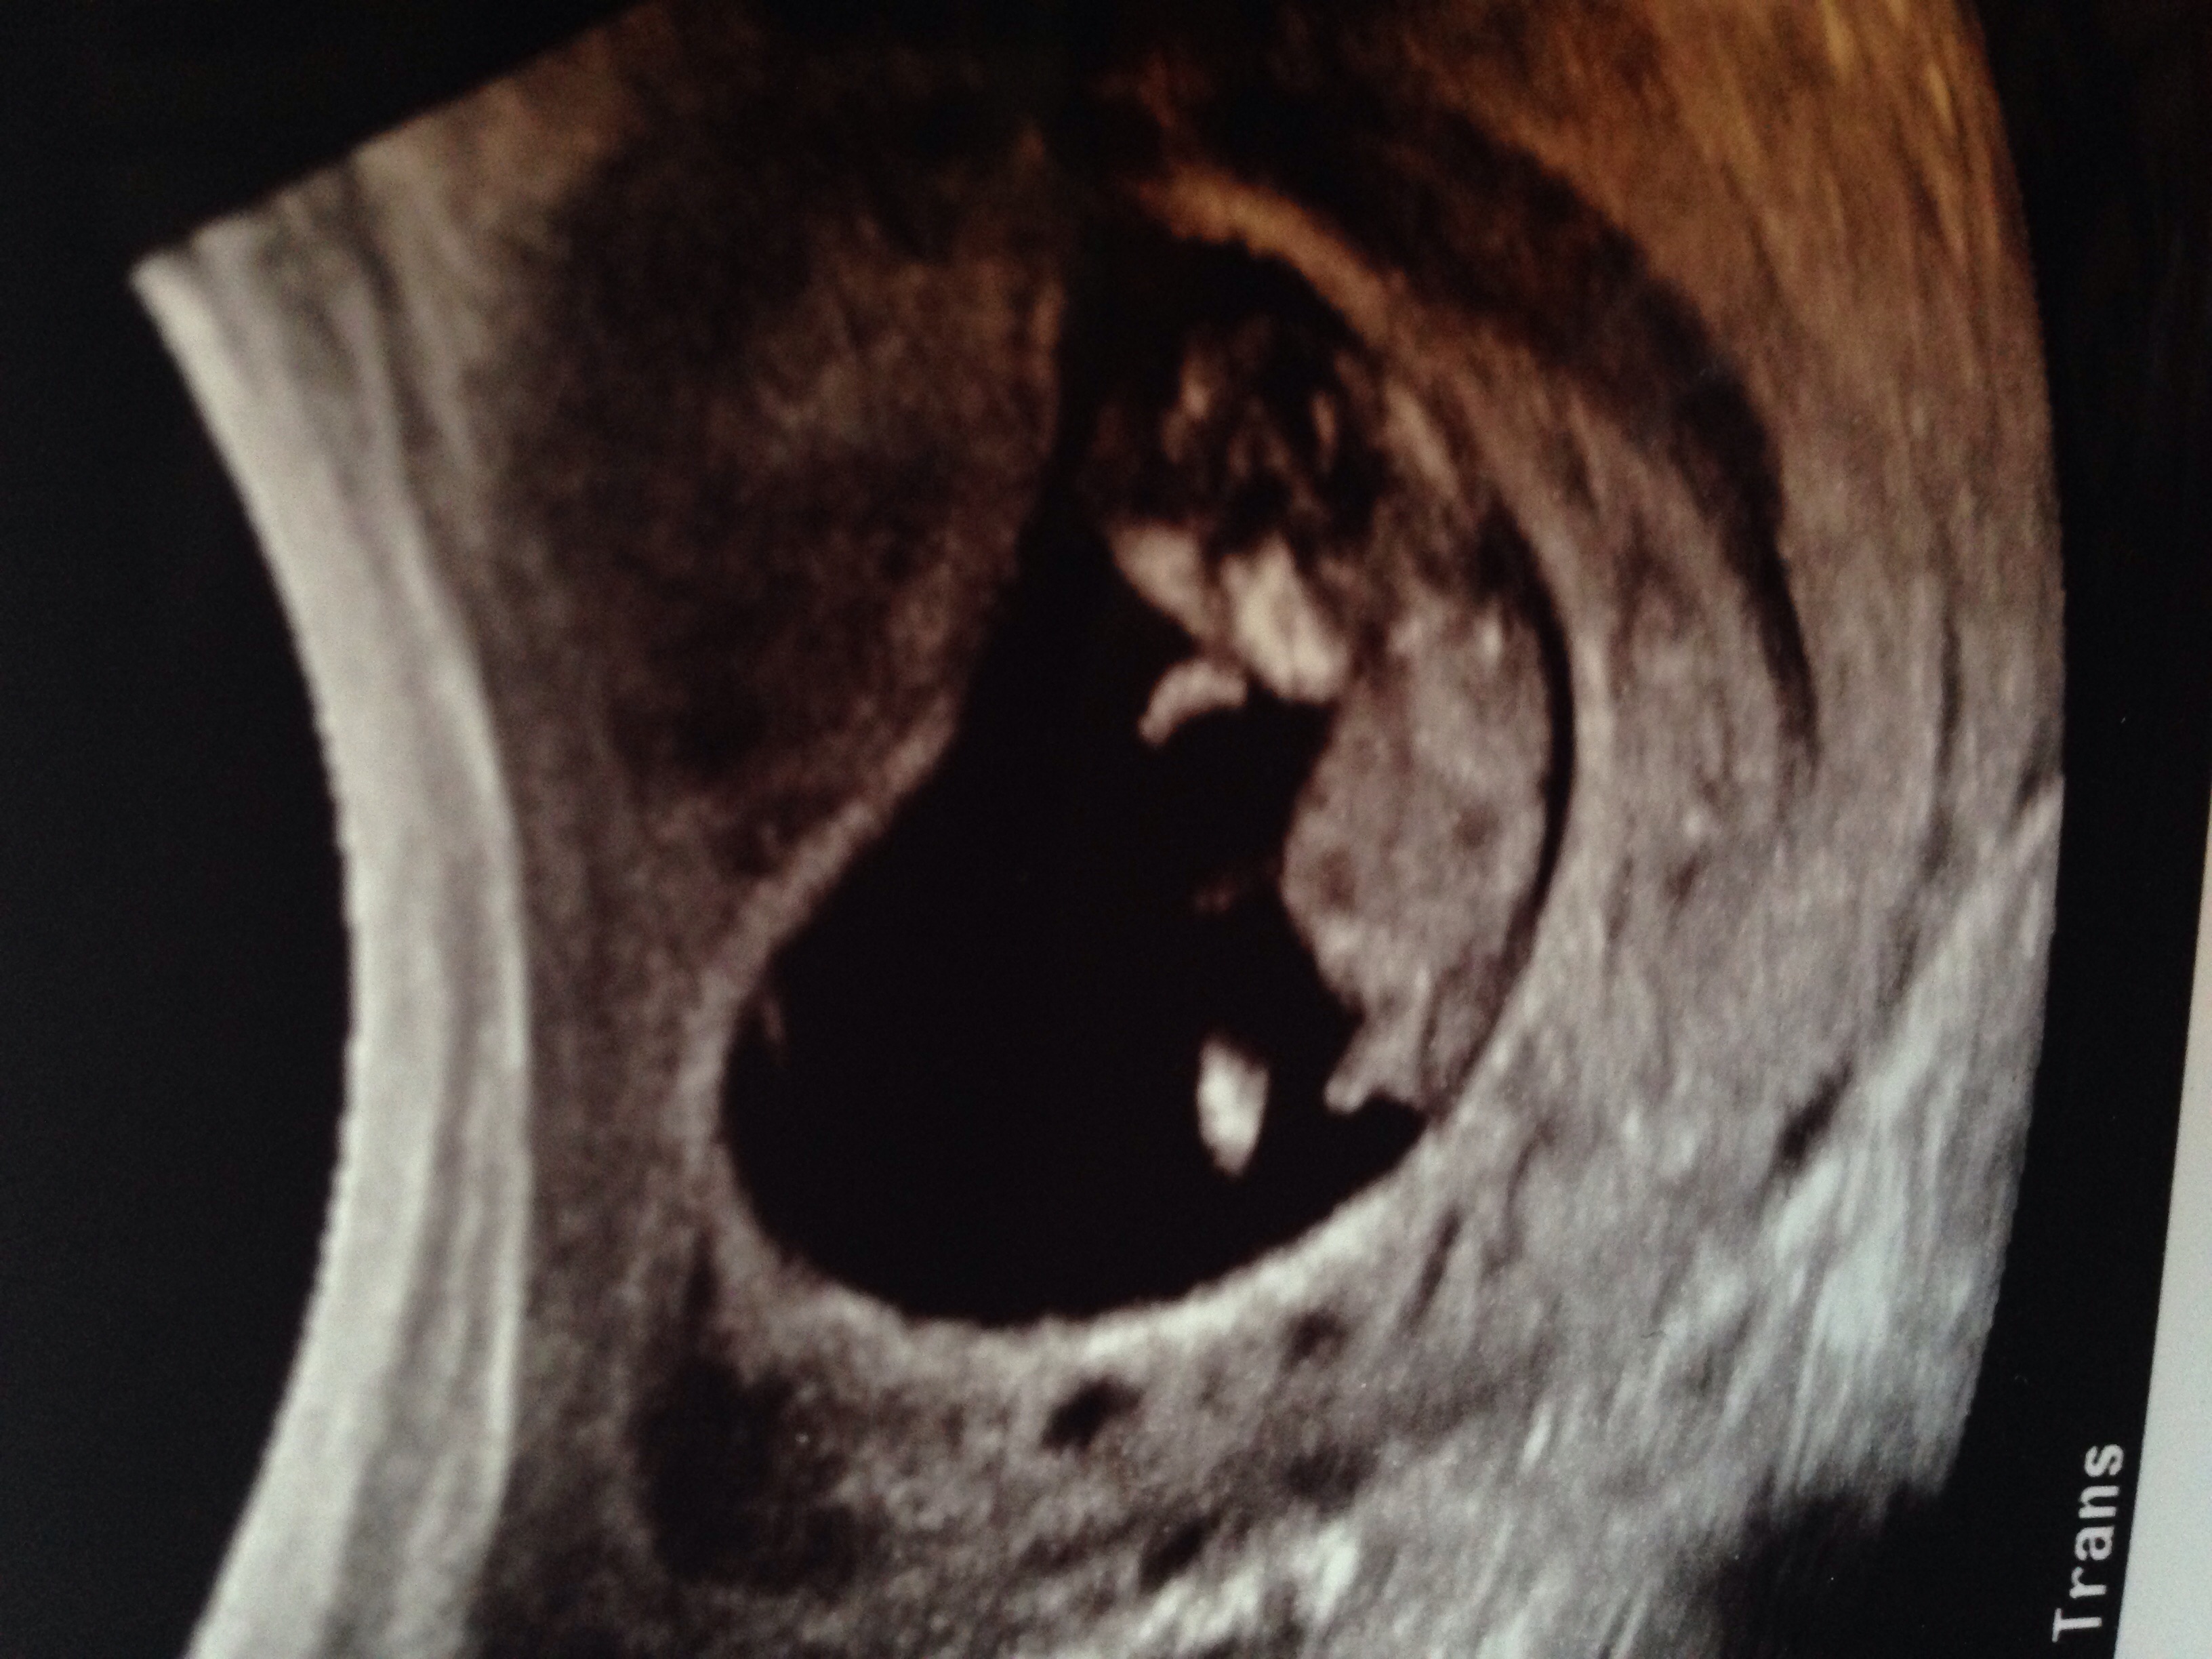

Just looking for guesses on boy or girl... 11 Weeks!Attachment 27581

Would say boy

boy! 从我的 iPhone 发送,使用 Tapatalk

Boy Sent from my iPhone using Tapatalk